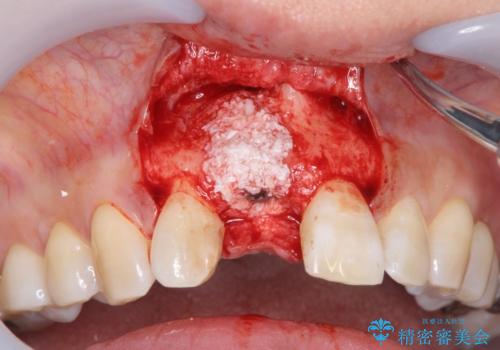

審美的・機能的に良好な位置に埋入するには、骨量が十分ではなかったため骨の造成を併用したインプラント埋入外科手術を行います。

前歯のインプラントを審美的に仕上げるには、インプラント周囲に十分な骨の量と厚みのある歯肉、そして埋入位置の精密な位置付けが重要です。

- 外科手術のため、術後に痛みや腫れ、違和感を伴います